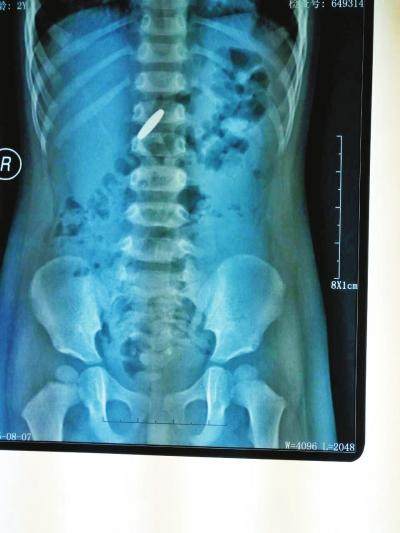

宝宝一旦吞食电池,很可能导致窒息。咽下后,被鼻涕、唾液或胃液浸润后,其中的化学物质可能会腐蚀食道和胃黏膜,造成内脏穿孔。一些尖锐的物件,如图钉,螺丝钉,铁钉,吞食会刺伤食管黏膜,胃黏膜。

硬币拍片在人体的位置